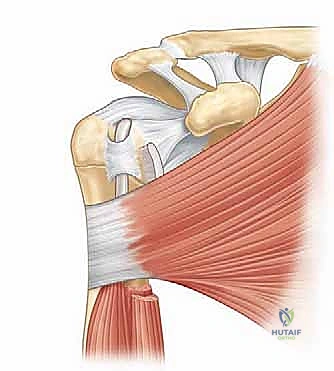

لفهم كيفية حدوث التهاب وتر العضلة ذات الرأسين ولماذا يكون مؤلماً للغاية، من الضروري والمحوري أولاً أن نغوص في تفاصيل تشريحه الفريد ودوره البيوميكانيكي في حركة مفصل الكتف. العضلة ذات الرأسين العضدية (Biceps Brachii) هي العضلة البارزة والكبيرة في الجزء الأمامي من العضد (الذراع العلوي). وكما يشير اسمها، فإن لها "رأسين" أو منشأين في منطقة الكتف: رأس قصير (Short Head) ورأس طويل (Long Head). اهتمامنا الطبي والجراحي في هذا السياق ينصب بشكل رئيسي على "الرأس الطويل للعضلة ذات الرأسين"، والذي يتميز بمساره التشريحي المعقد والفريد داخل وخارج مفصل الكتف.

ينشأ الرأس الطويل للعضلة ذات الرأسين من منطقة عظمية محددة في لوح الكتف تسمى "الحديبة فوق الحقانية" (Supraglenoid Tubercle)، وكذلك من الجزء العلوي من "الشفا الحقاني" (Glenoid Labrum) – وهو عبارة عن حلقة غضروفية ليفية قوية تحيط بتجويف الكتف الضحل وتعمل على تعميقه لزيادة استقرار المفصل.

بعد نقطة المنشأ هذه، يسلك الوتر مساراً مميزاً واستثنائياً في جسم الإنسان: فهو يدخل فعلياً داخل كبسولة مفصل الكتف (Intra-articular) ولكنه يظل خارج الغشاء الزليلي المبطن للمفصل (Extra-synovial). يقطع الوتر مسافة تتراوح بين 35 إلى 55 ملم في المتوسط كجسر معلق داخل المفصل، قبل أن ينعطف بزاوية حادة ليخرج من المفصل عبر ممر عظمي ضيق يُعرف باسم "التلم ثنائي الرأس" أو الأخدود ذو الرأسين (Bicipital Groove) الموجود في الجزء الأمامي من عظم العضد. هذا المسار التشريحي الفريد، والانعطاف الحاد، والوجود داخل ممر عظمي ضيق، يجعل هذا الوتر عرضة بشكل استثنائي للاحتكاك، الضغط، والإصابات الميكانيكية.

عند نقطة خروج وتر العضلة ذات الرأسين من مفصل الكتف ودخوله في الأخدود العظمي، نصادف بنية تشريحية حاسمة ومعقدة تسمى "مركب بكرة العضلة ذات الرأسين" (Biceps Pulley Complex). هذا المركب لا يتكون من عظم، بل من شبكة دقيقة من الأربطة والأوتار، وتحديداً:

هذا النظام التشريحي الشبيه بالبكرة الميكانيكية ضروري للغاية للحفاظ على استقرار الرأس الطويل للعضلة ذات الرأسين داخل التلم ثنائي الرأس أثناء حركة الكتف. إذا حدثت إصابة أو تمزق في مركب البكرة هذا (وهو أمر شائع في الإصابات الرياضية أو مع التقدم في العمر)، فإن وتر العضلة ذات الرأسين يفقد ثباته ويبدأ في الانزلاق الجزئي (Subluxation) أو الخلع الكامل (Dislocation) من مساره الطبيعي، غالباً نحو الداخل والأسفل. هذا الخلع يسبب احتكاكاً مدمراً، مما يؤدي إلى أعراض ميكانيكية مثل "الطقطقة" أو "الفرقعة" المسموعة والمحسوسة، مصحوبة بتغيرات تنكسية وتمزقات إضافية في الوتر نفسه وفي أوتار الكفة المدورة المجاورة.